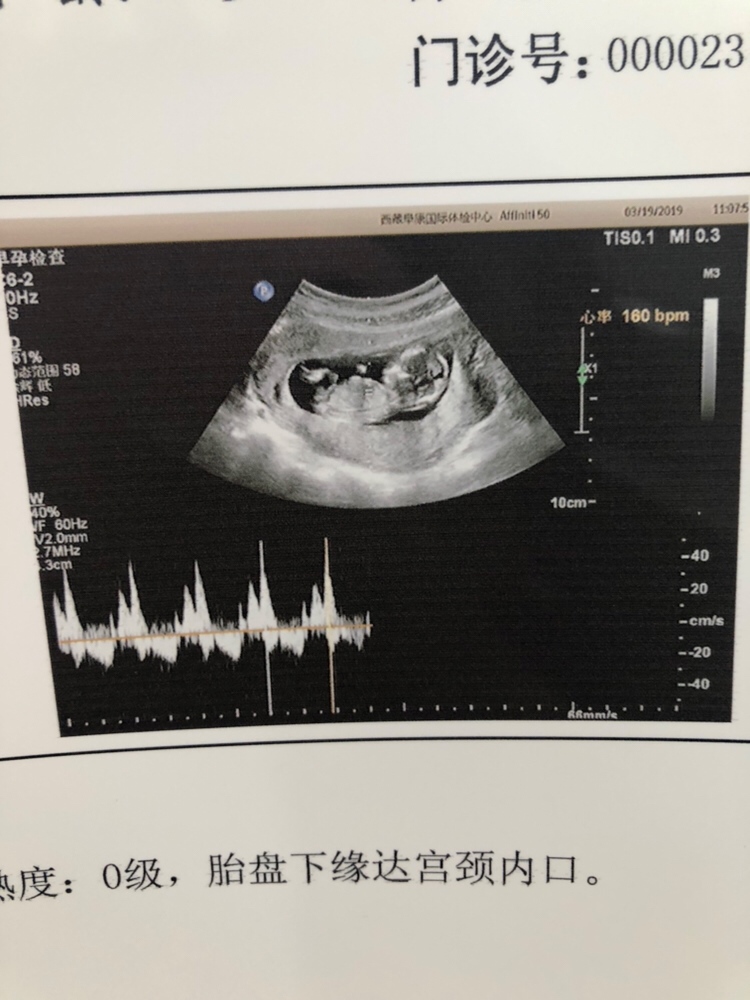

孕16周+3天

按之前计算的,医生说的那个是胎儿的大小,我检查完NT胎儿也偏大